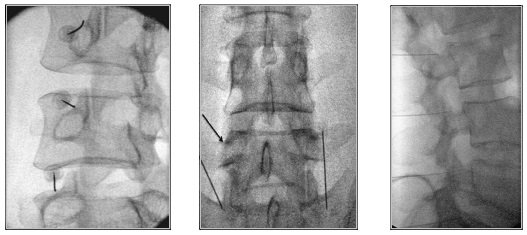

Πώς εκτελείται η διαδικασία νευρικού αποκλεισμού της άρθρωσης

Η διαδικασία μπορεί να διενεργηθεί στις αρθρώσεις του αυχένα, της ράχης και της μέσης. Με τον ασθενή σε πρηνή θέση και υπό τοπική αναισθησία εισάγεται μια βελόνα που υπό συνεχή ακτινοσκοπική καθοδήγηση φθάνει στους νευρικούς κλάδους της κάθε άρθρωσης. Μια μικρή ποσότητα αναισθητικού διαλύματος εγχέεται και αφαιρείται η βελόνα. Ο ασθενής αναπαύεται για 30 λεπτά και σε μία ώρα μπορεί να εξέλθει, μετά την αξιολόγησή του από τον θεράποντα ιατρό. Οι κίνδυνοι από τη διαδικασία είναι σπάνιοι.

Χορηγείται τοπική αναισθησία για να μουδιάσει το δέρμα. Ο ιατρός κάτω από ακτινοσκοπική καθοδήγηση, εισάγει μια λεπτή ειδική βελόνα που στοχεύει το σημείο διέλευσης του μέσου νευρικού κλάδου, το οποίο βρίσκεται στη συμβολή της άνω αρθρικής και της εγκάρσιας απόφυσης του σπονδύλου στην οσφυϊκή μοίρα.

Στην πορεία ακολουθεί κινητικός και αισθητικός ερεθισμός του νεύρου. Αυτό μπορεί να οδηγήσει σε μικρούς τοπικούς μυϊκούς σπασμούς και να προκαλέσει λίγο πόνο. Μόλις ελεγχθεί η σωστή τοποθέτηση της βελόνας, χορηγείται τοπικό αναισθητικό και ακολουθεί η θερμοκαυτηρίαση του νεύρου.